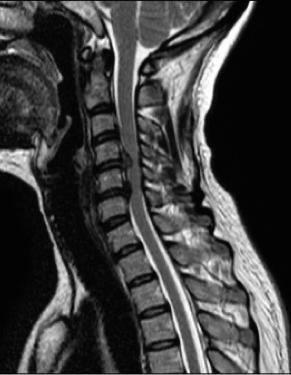

Injury to spinal cord (cervical, thoracic) high spinal anaesthesia.

- Loss of sympathetic tone due to cord injury

- Hypotension, warm well perfused limbs, diminished/absent motor function

- Bradycardia